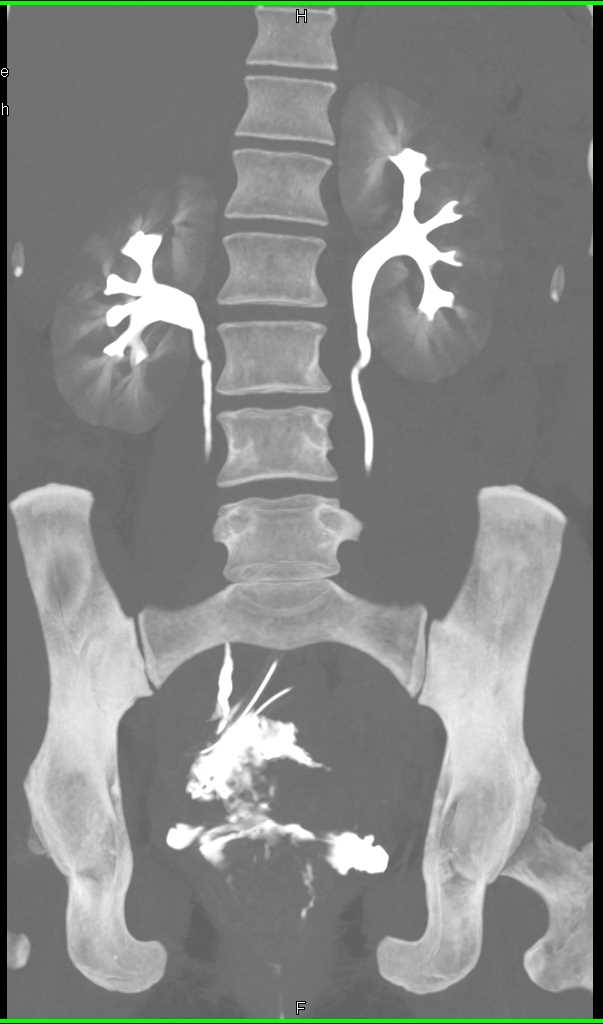

Extravasation from the Bladder